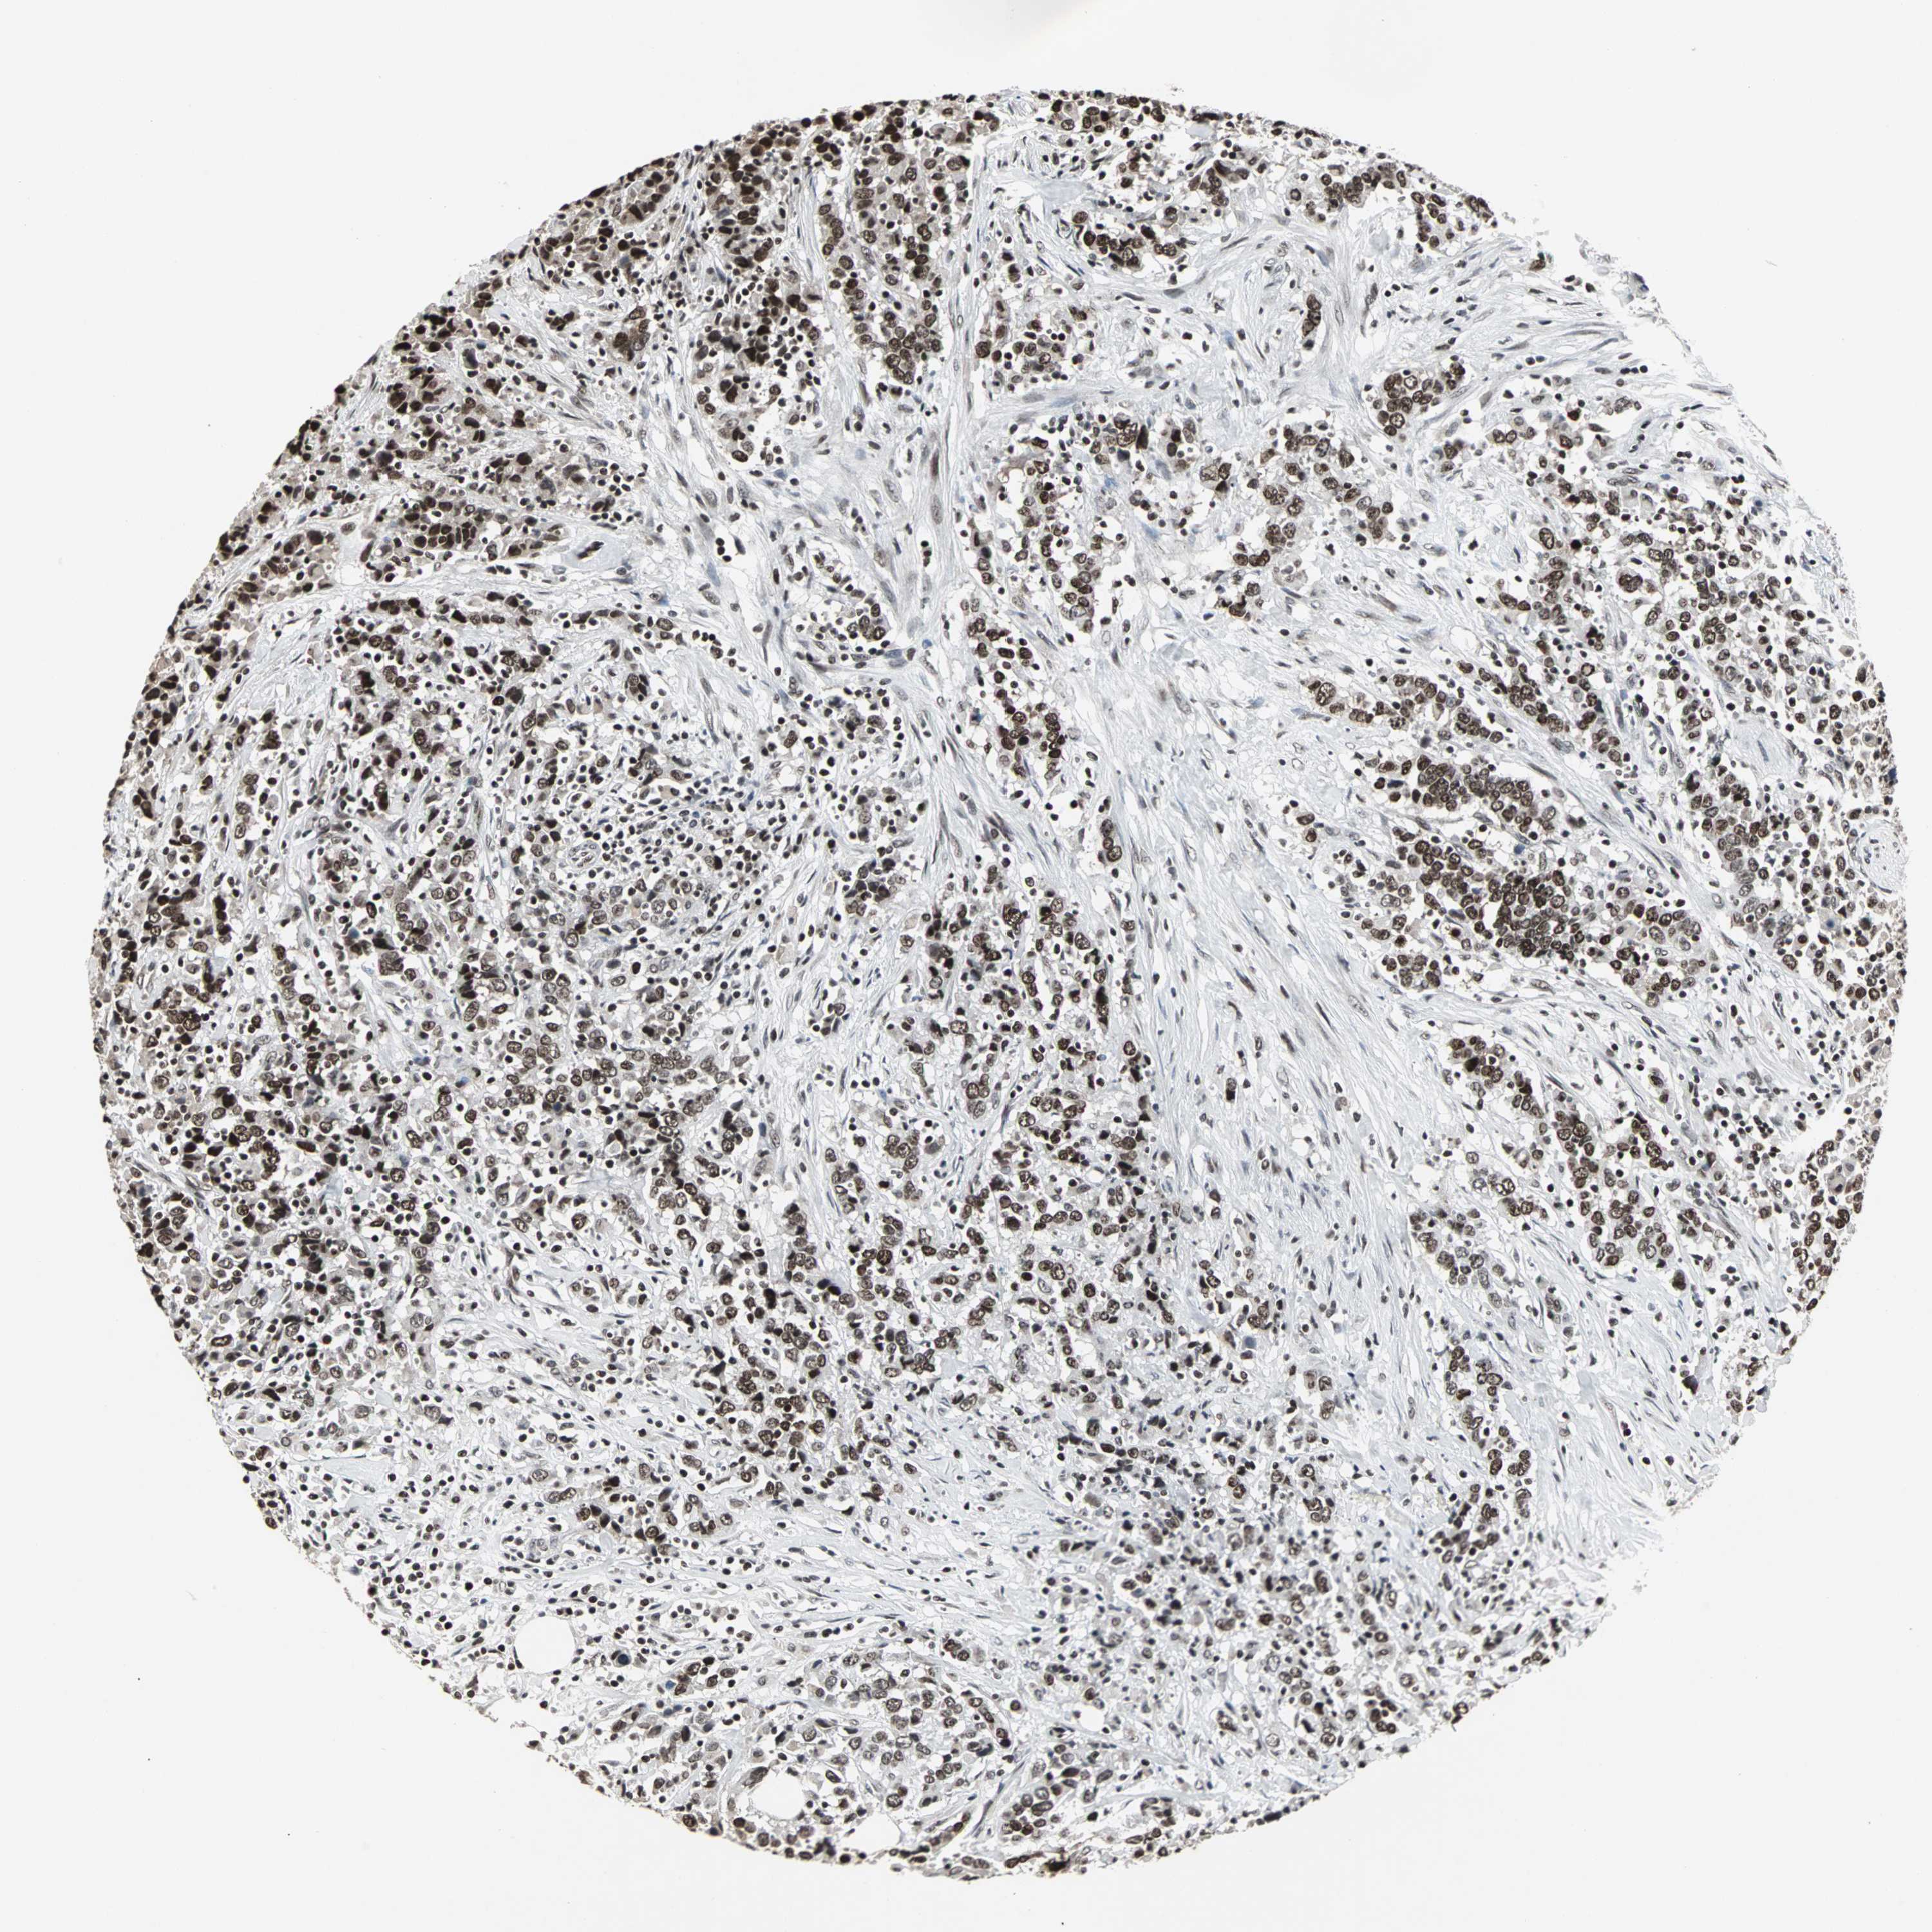

UROTHELIAL CANCER - Protein expressioni

A mouse-over function shows sample information and annotation data. Click on an image to view it in a full screen mode. Samples can be filtered based on level of antibody staining by selecting one or several of the following categories: high, medium, low and not detected. The assay and annotation is described here.

Note that samples used for immunohistochemistry by the Human Protein Atlas do not correspond to samples in the TCGA dataset.

Antibody stainingi

Antibody staining in the annotated cell types in the current human tissue is reported as not detected, low, medium, or high, based on conventional immunohistochemistry profiling in selected tissues. This score is based on the combination of the staining intensity and fraction of stained cells.

Each image is clickable and will lead to virtual microscopy that enables deeper exploration of all samples and also displays staining intensity scores, fraction scores and subcellular localization as well as patient and tissue information for each sample.

Antibody HPA006782

Staining

High

Medium

Low

Not detected

Intensity

Strong

Moderate

Weak

Negative

Quantity

>75%

75%-25%

<25%

None

Location

Nuclear

Cytoplasmic/membranous

Cytoplasmic/membranous,nuclear

Urothelial carcinoma, High grade

Urothelial carcinoma, Low grade